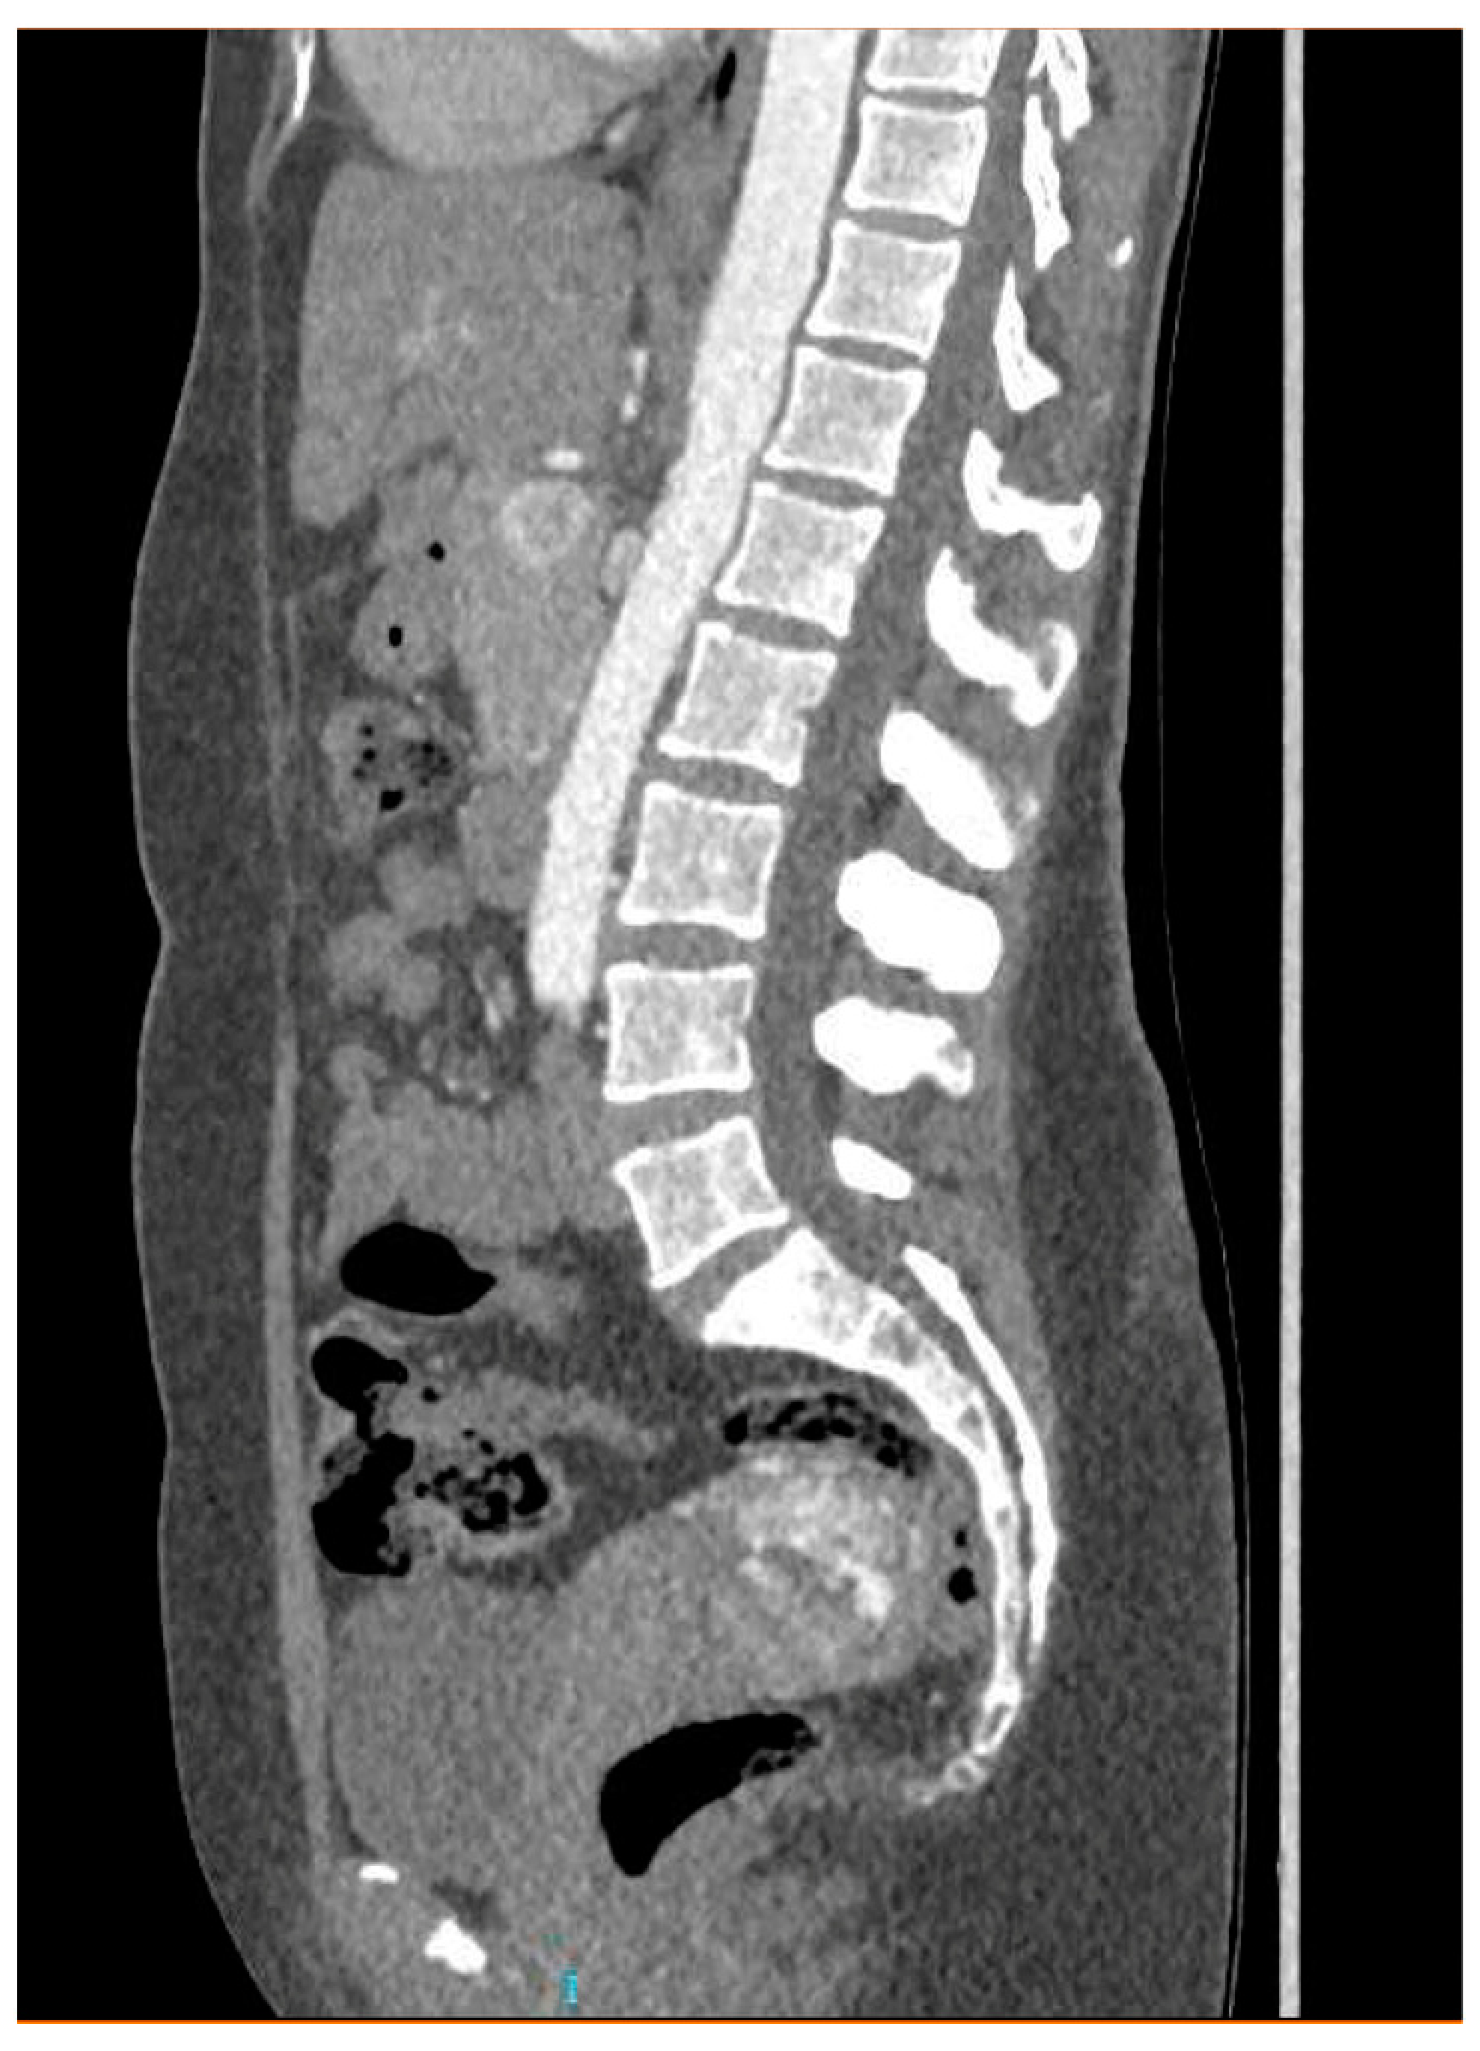

Ultrasonography showed an endometrial cavity occupied by a protruding formation in the uterine cavity measuring 38 × 15 mm, compatible with a uterine AVM (Figure 1). The presence of vascularisation of the right lateral uterine wall was noted, and pulsed Doppler showed a peak systolic velocity > 100 cm/s (Figure 2).

CT angiography showed a complex network of millimetre-sized vessels of tortuous appearance with rapid contrast enhancement in the late arterial phase and isodensity in the portal phase (similar to systemic venous vessels). This network extended through the right parametrium, through the myometrial fundus, and apparently into the endometrium (Figure 3 and Figure 4). The radiological findings were compatible with a uterine arteriovenous malformation.

Figure 2. Colour and pulsed Doppler studies of the uterine arteriovenous malformation.